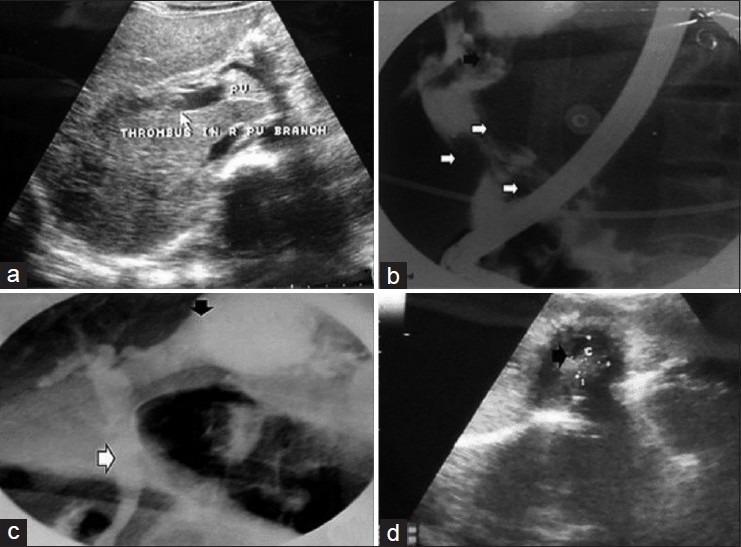

Hydatid cyst of liver complicated with budd-Chiari syndrome and portal vein thrombosis.

https://cdn.ncbi.nlm.nih.gov/pmc/blobs/49ca/3632032/191e1ea0557e/NAJMS-5-242-g002.jpg